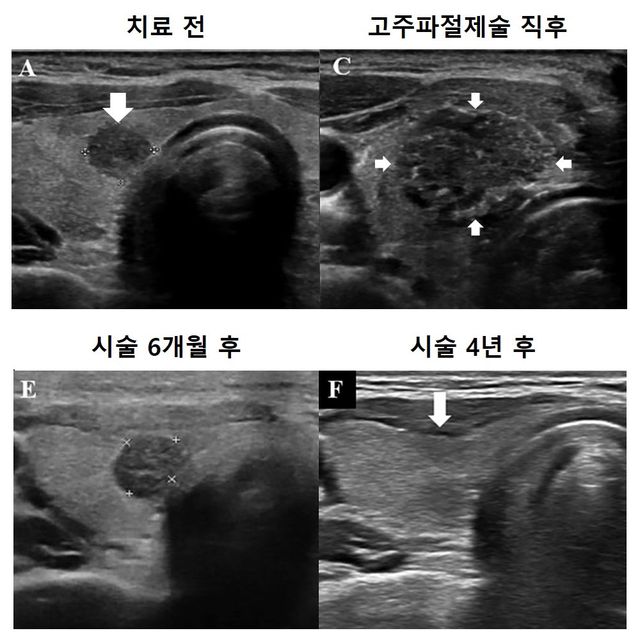

종양 크기 1cm 이하인 미세갑상선유두암은 진행 속도가 느리고 예후가 좋은 암이다. 치료 옵션으로 갑상선 절제수술 또는 적극적 관찰이 권고된다. 고주파 절제술은 미세한 바늘을 삽입해 고열로 종양과 주변 조직을 괴사시키는 치료법으로, 괴사한 조직은 시간이 지나면 자연스럽게 사라진다.

추적 관찰 결과, 절제 영역은 시술 후 지속적으로 감소해 최종 추적 관찰 시 전체 환자의 95.9%에서 완전히 사라졌다. 암 진행률은 3%로 대부분의 환자는 암이 커지거나 전이되지 않았다. 부작용으로 1명에게서 일시적인 성대 마비가 발생했으나, 이는 6개월 후 회복됐으며 다른 합병증은 전체 추적 관찰 기간 발생하지 않았다.